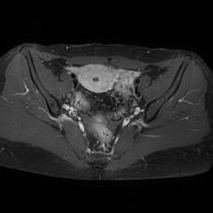

MRI(Magnetic Resonance Imaging/磁気共鳴画像)は、強力な磁石と電波を用いて体の内部を詳しく撮影する検査です。

放射線被ばくがなく痛みもない安全な検査です。通常20~40分程度で終わります。

脳だけでなく、全身のさまざまな部位の検査が可能です。

脳・脊椎・関節・四肢・腹部・骨盤・乳腺など幅広い部位に対応しています。

当院では最新の3テスラMRI装置を導入しており、従来の1.5テスラ装置とあわせて検査内容に応じた撮影を行っています。

3T MRIでは、高精細でより詳細な画像診断が可能です。